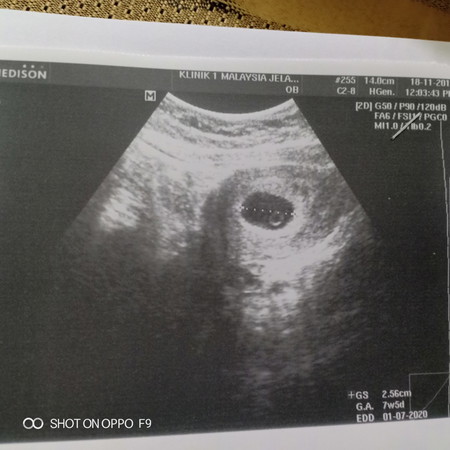

Normal ke kalau kira ikut last period kita dah masuk 10 minggu tapi bila scan doktor kata pelik sbb tak nampak baby, cuma ada kantung je. Kt album scan bru masuk 7 minggu lebih. Ada yang pernah jadi macam ni tak? Saya cuak sebab doktor kata mungkin baby masih kecil atau hanya kantung sahaja ?

scan ke dua pada 29/10 . 7w dh nmpk tp halus jaa . kabur2 juga. third scan baru jelas